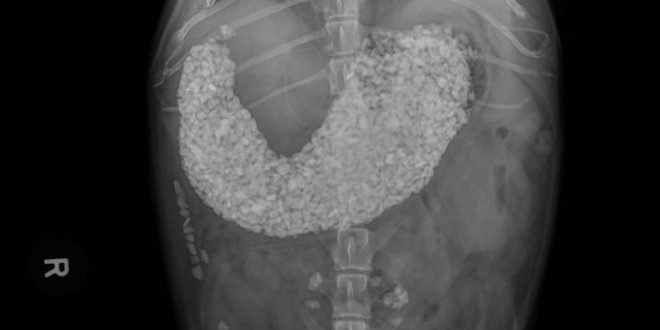

收好你的襪子、黃色小鴨跟燈泡!不然它們會出現在你家毛小孩胃裡!

xray-toby